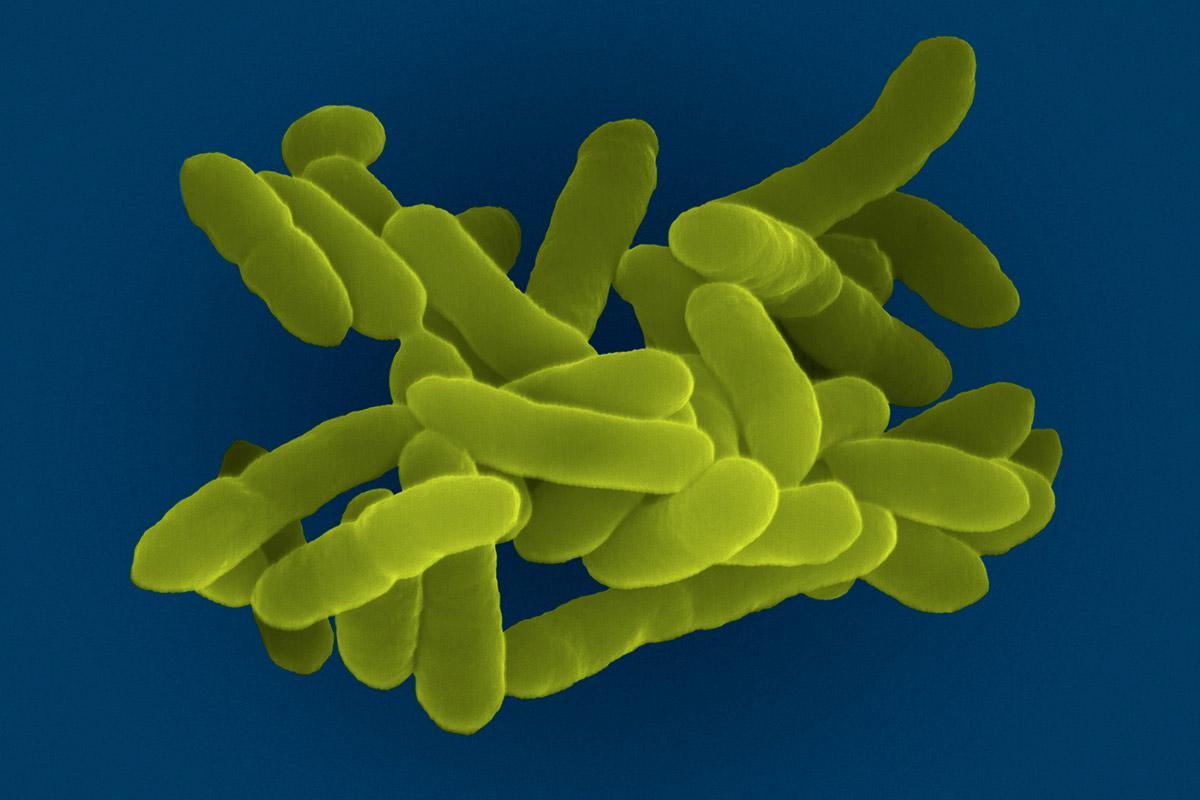

Фотографии бактерий, вызывающих бактериальные пневмонии у животных

Раздел: Другие животные